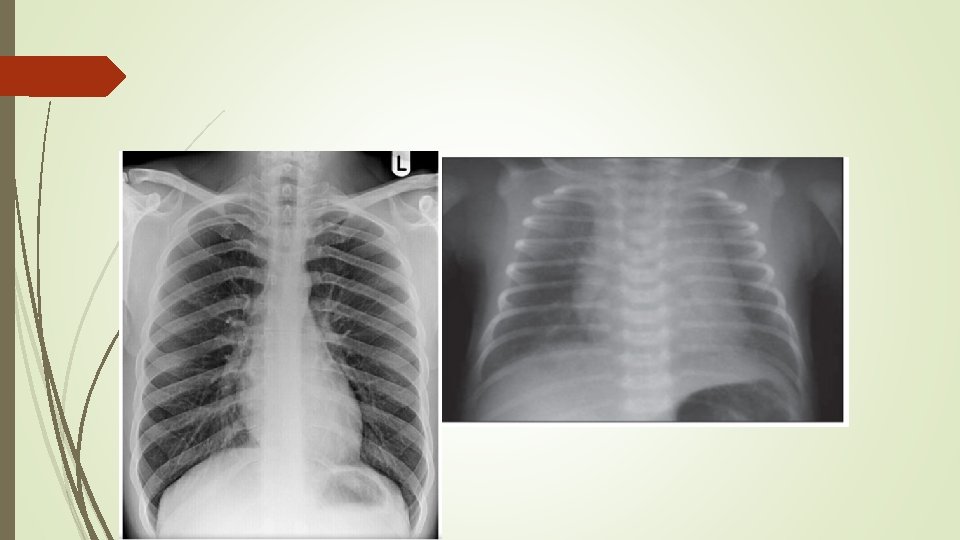

Pediatric imaging Learning objectives 1 Systemic approach interpretation